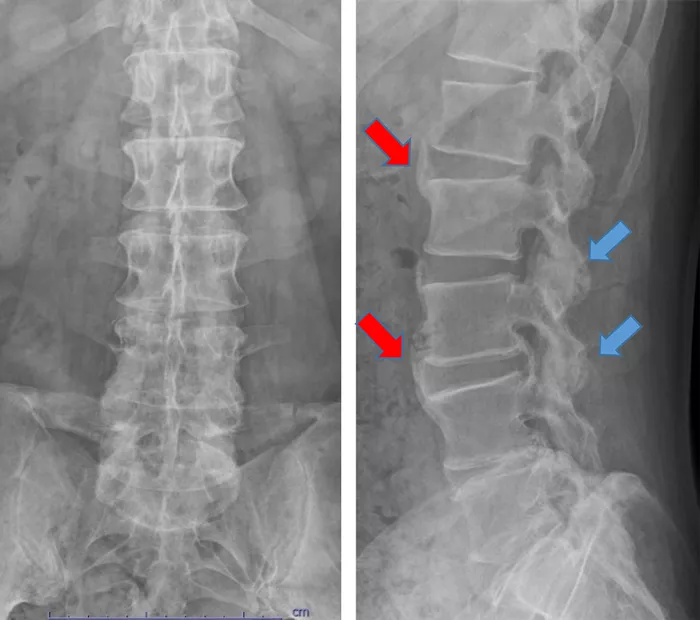

写真2

椎体前方に一部STIR画像で高輝度の炎症所見あり(赤矢印)。

L4/5とL5/S1の椎体の終板には脂肪変性あり(青矢印)。

L3/4には、中等度の脊柱管狭窄あり(黄矢印)。